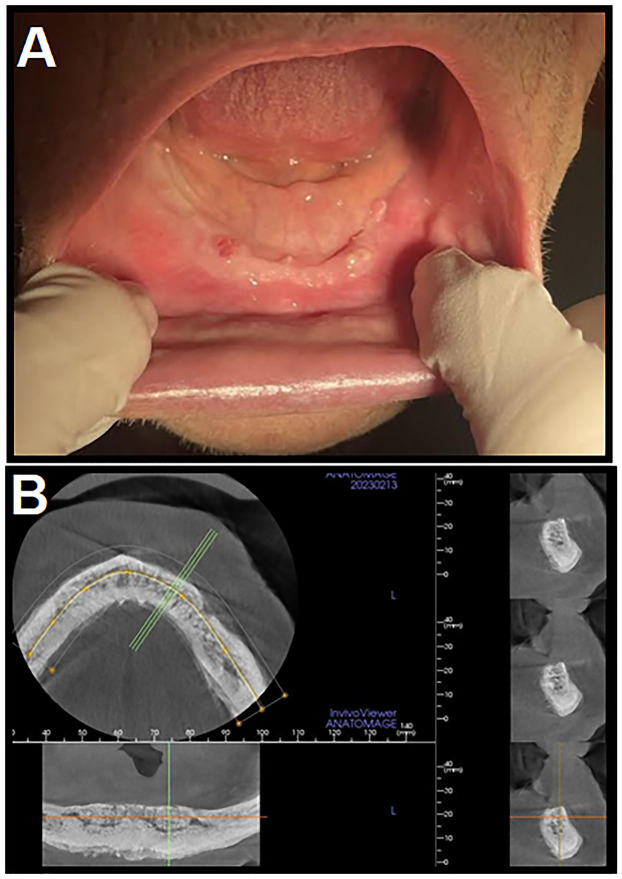

药物相关性颌骨骨坏死(MRONJ)是抗吸收治疗的一种日益常见的后果,它通常导致坏死暴露的骨表面的发展,并伴有影响颌骨的炎症过程。虽然MRONJ的发展通常与口腔微生物群定植成员引起的炎症反应或感染有关,但MRONJ的确切发病机制尚不完全清楚。在本文中,我们旨在提供额外的微生物培养支持的证据,支持“感染假说”,即放线菌及其相关生物可能在MRONJ的发展和导致的骨坏死中发挥重要的致病作用。在我们的病例系列中,所有患者都有相似的基础疾病和遗忘数据,并接受了抗吸收药物(双膦酸盐或RANK配体(RANKL)抑制剂),以预防继发于前列腺癌的骨转移的发生或进展。然而,在抗吸收药物治疗的几年中,在上述患者中发现了不同阶段的MRONJ。在所有三个病例中,坏死骨样本的定量微生物培养产生了一个复杂的微生物群,以放线菌和沙利亚菌为主,菌落数量高。此外,我们的随访病例系列记录了这些患者联合手术干预和长期抗生素治疗的治疗情况,所有病例都有良好的临床反应。如果“感染假说”是有效的,它可能对与该疾病相关的预防和治疗策略产生重大影响。

Medication-related osteonecrosis of the jaw (MRONJ) is an increasingly common consequence of antiresorptive treatment, which often leads to the development of necrotic exposed bone surfaces with inflammatory processes affecting the jawbone. Although the development of MRONJ is often associated with the inflammatory response or infections caused by the colonizing members of the oral microbiota, the exact pathogenesis of MRONJ is still not fully understood. In the present paper, we aimed to provide additional, microbiological culture-supported evidence, supporting the "infection hypothesis" that Actinomyces spp. and related organisms may play an important pathogenic role in the development of MRONJ and the resulting bone necrosis. In our case series, all patients presented with similar underlying conditions and anamnestic data, and have received antiresorptive medications (bisphosphonates or a RANK ligand (RANKL) inhibitor) to prevent the occurrence or progression of bone metastases, secondary to prostate cancer. Nevertheless, a few years into antiresorptive drug therapy, varying stages of MRONJ was identified in the mentioned patients. In all three cases, quantitative microbiological culture of the necrotic bone samples yielded a complex microbiota, dominated by Actinomyces and Schaalia spp. with high colony counts. Additionally, our followed-up case series document the treatment of these patients with a combination of surgical intervention and long-term antibiotic therapy, where favourable clinical responses were seen is all cases. If the "infection hypothesis" is valid, it may have significant consequences in the preventative and therapeutic strategies associated with this disease.